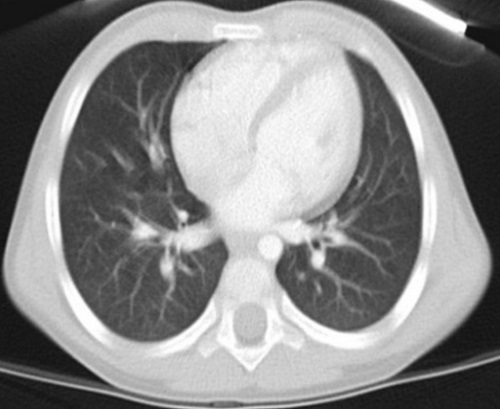

Ante la evolución tórpida de la imagen radiológica, se solicitó tomografía computarizada (TC) de tórax con contraste (Fig. 2) y angioTC, en el que se objetiva lesión en LID compatible con malformación vascular. Ante esta sospecha, se decide realizar angiografía (Fig. 3), donde se confirma el diagnóstico de malformación venosa pulmonar, no subsidiara de tratamiento intervencionista. Por este motivo, se decide iniciar tratamiento empírico con propanolol a 2 mg/kg/día. A los 6 meses se solicita TC de control, en el que se observa importante reducción de la malformación venosa. Al finalizar el tratamiento se realizó nuevo TC de tórax, en el que se objetiva la desaparición de la lesión focal de tipo vascular del LID.

Figura 3. Principales imágenes radiológicas del caso: fluoroscopia al diagnóstico